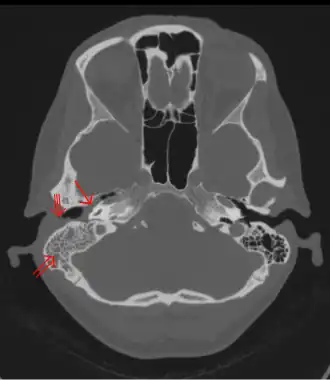

CT scan: Otitis media (simple arrow) and mastoiditis (double arrow) of the right side (left side in image). The external auditory canal is partially occupied by suppuration (triple arrow). 44-year-old woman.

The diagnosis of mastoiditis is clinical—based on the medical history and physical examination. Imaging studies provide additional information; The standard method of diagnosis is via MRI scan although a CT scan is a common alternative as it gives a clearer and more useful image to see how close the damage may have gotten to the brain and facial nerves. Planar (2-D) X-rays are not as useful. If there is drainage, it is often sent for culture, although this will often be negative if the patient has begun taking antibiotics. Exploratory surgery is often used as a last resort method of diagnosis to see the mastoid and surrounding areas.[2][9]